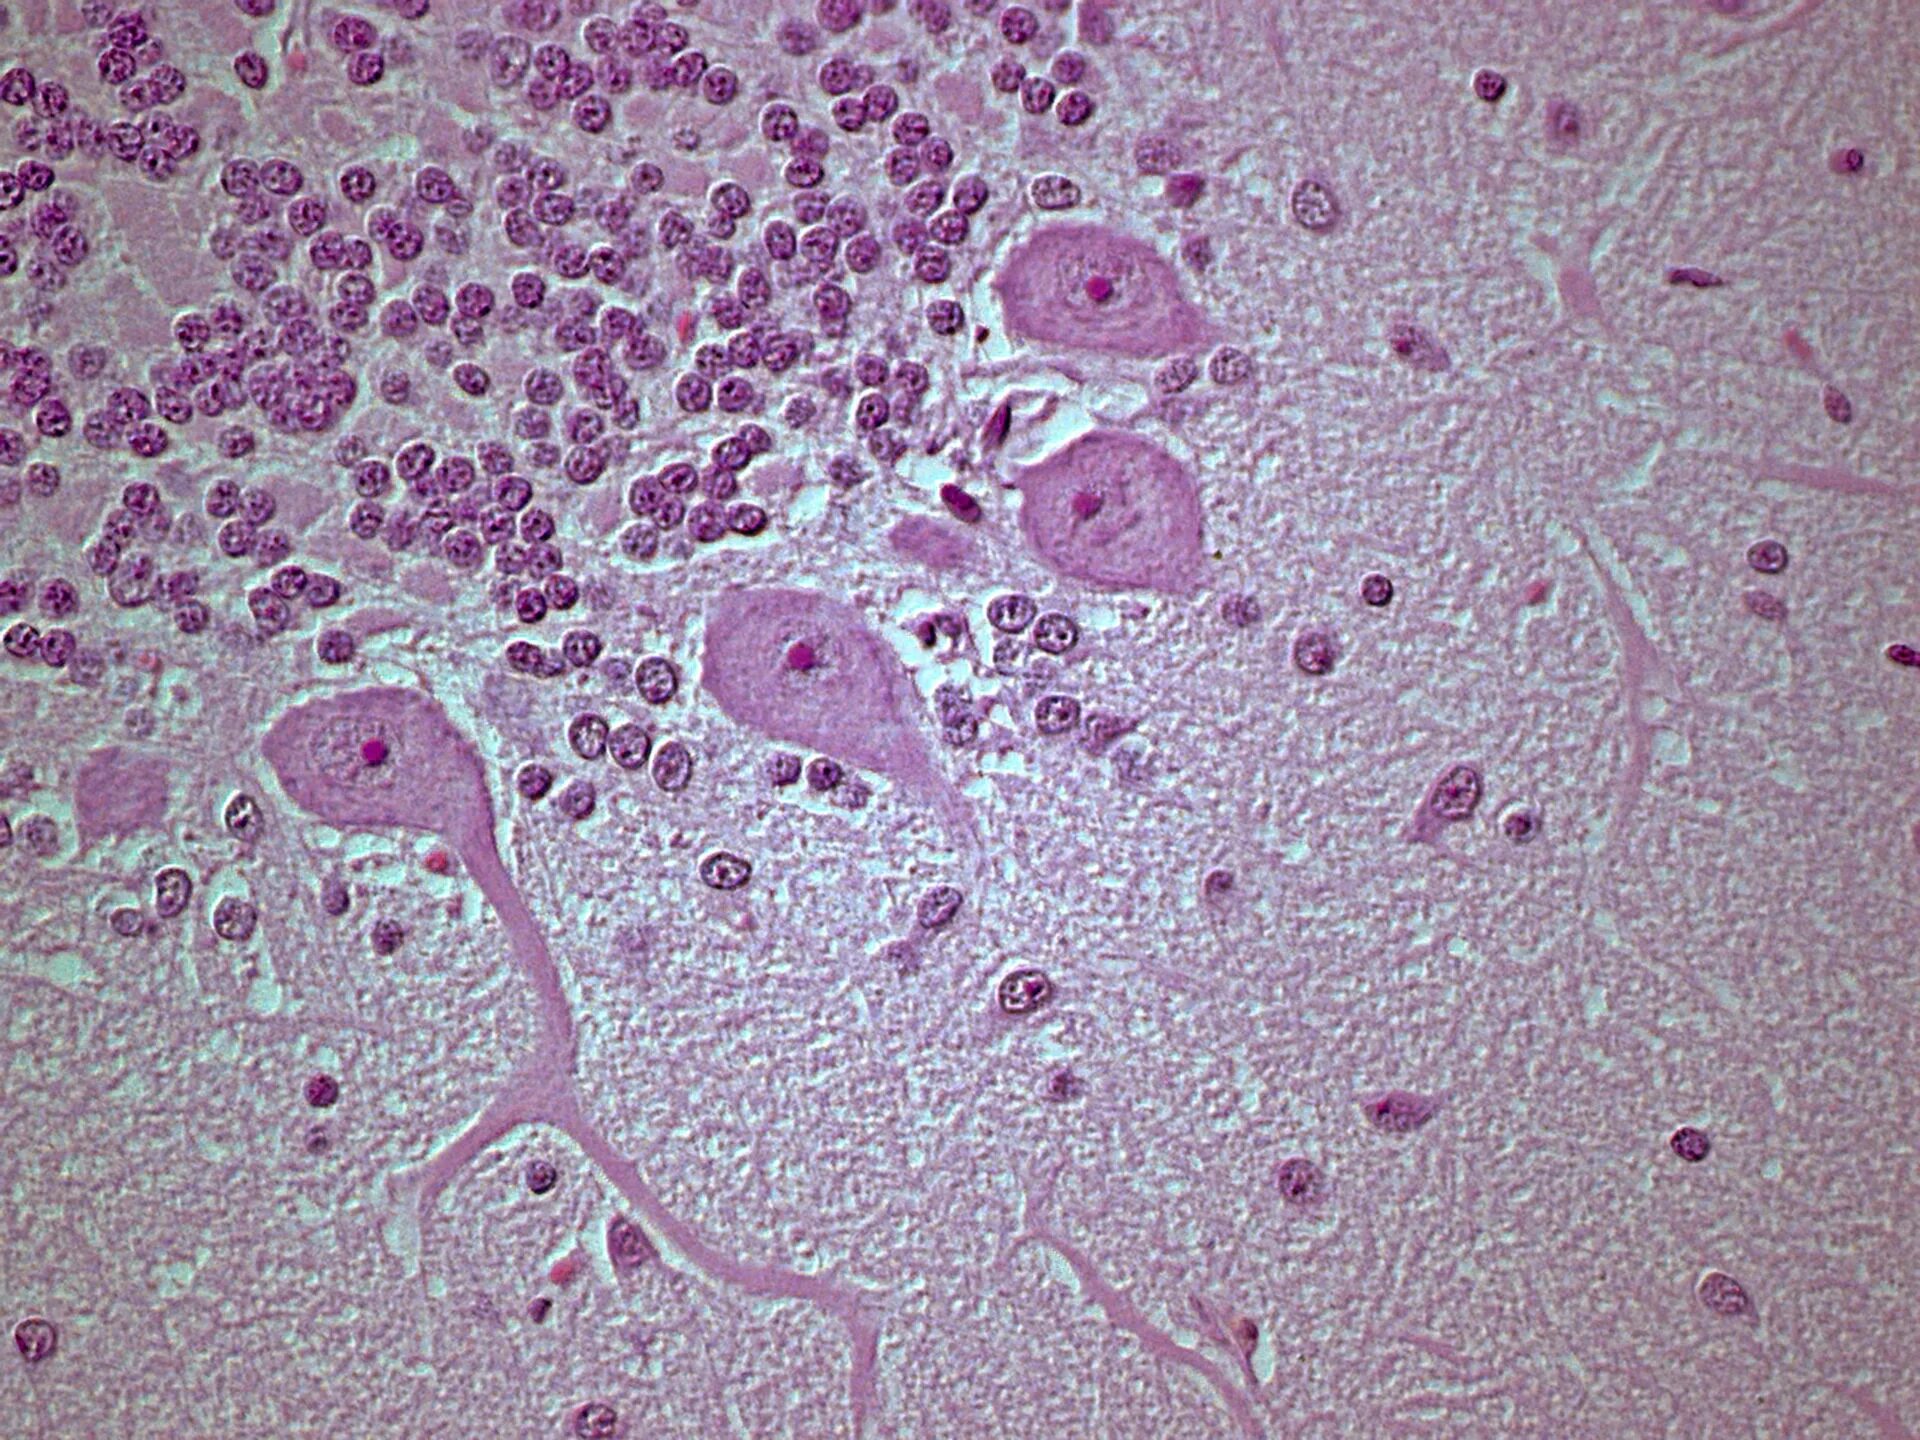

Гистология э